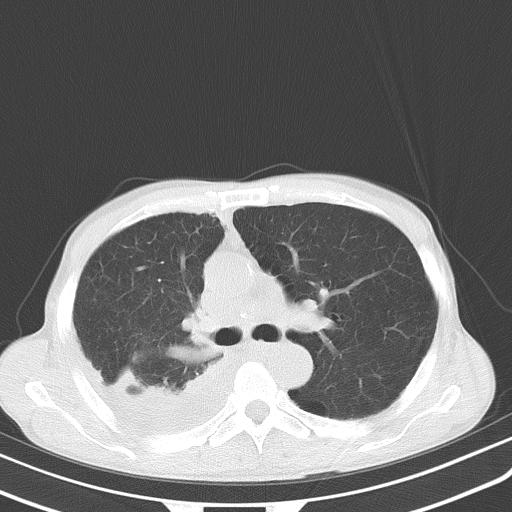

男性 75  咳嗽 一周前发热最高达39

右肺继发型tb并右侧tb性胸腔炎,右侧胸腔大量积液并右下肺膨胀不全,慢支肺气肿、多发肺大泡。建议抽胸水实验室检查并复查排除恶性在占位。

右上肺继发型肺结核,右胸腔中等量积液。

左上肺大泡。

结核的基础上有纵隔淋巴结肿大,右侧有胸水,但右侧纵隔反而窄,说明有肺有不张。

再就是右下肺有块影,和不张混合,还是不能除外肺癌。

补充材料,患者2月份ct片大致正常,双侧胸腔积液,2月份抽胸水未发现ca细胞,现患者发热,痰多,各气管通畅,